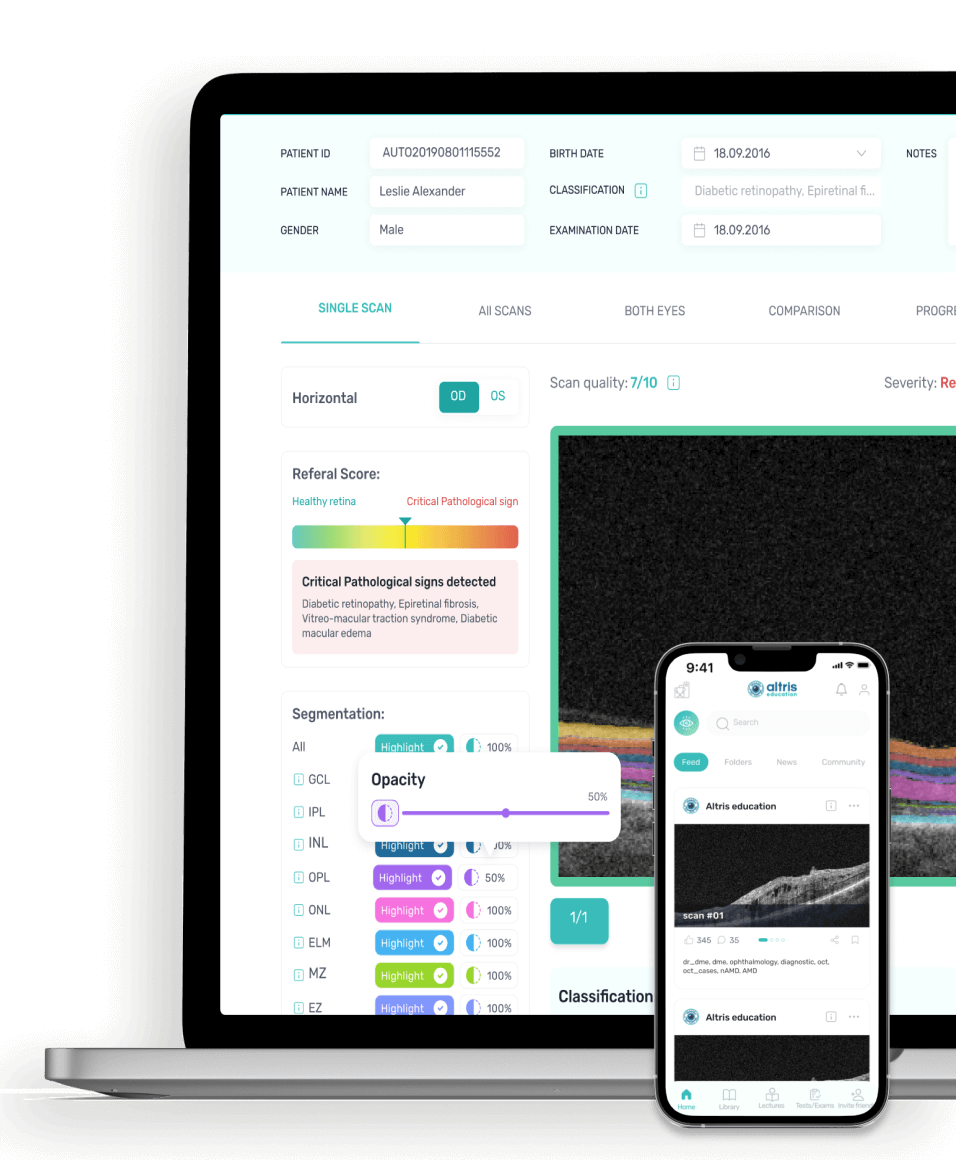

An innovative web and mobile app for Optical Coherence Tomography interpretation.